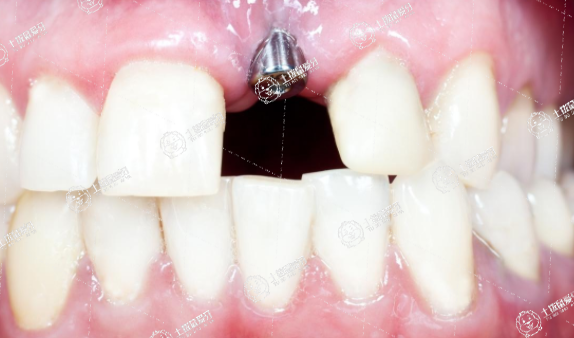

種植牙是效果是牙齒修復(fù)里面最好的,種植牙雖然不是人類天然長出來的牙齒,但是人工牙根在植入牙床后能夠與骨組織完全融合,而成為身體的一部分。至今,種植牙臨床應(yīng)用已超過40年,全世界每年有數(shù)以百萬計的牙種植體為患者解決了缺牙的痛苦

種植系統(tǒng)在生產(chǎn)工藝、外形設(shè)計、連接方式、加工精度、上部結(jié)構(gòu)以及消毒包裝等方面都有嚴格的要求及標準。不同的種植系統(tǒng)及材料就會有不同的效果,而這個也是決定種植出來的牙齒能維持多久的效果的重要因素了。

種植牙手術(shù)屬外科手術(shù),其對修復(fù)技術(shù)的精度要求極高,醫(yī)生必須接受過專門的學習和培訓。同時具有一定的臨床經(jīng)驗,才能正確完成種植治療的每一個步驟,順利處理治療過程中遇到的各種特殊情況,從而保證種植牙的長期效果。